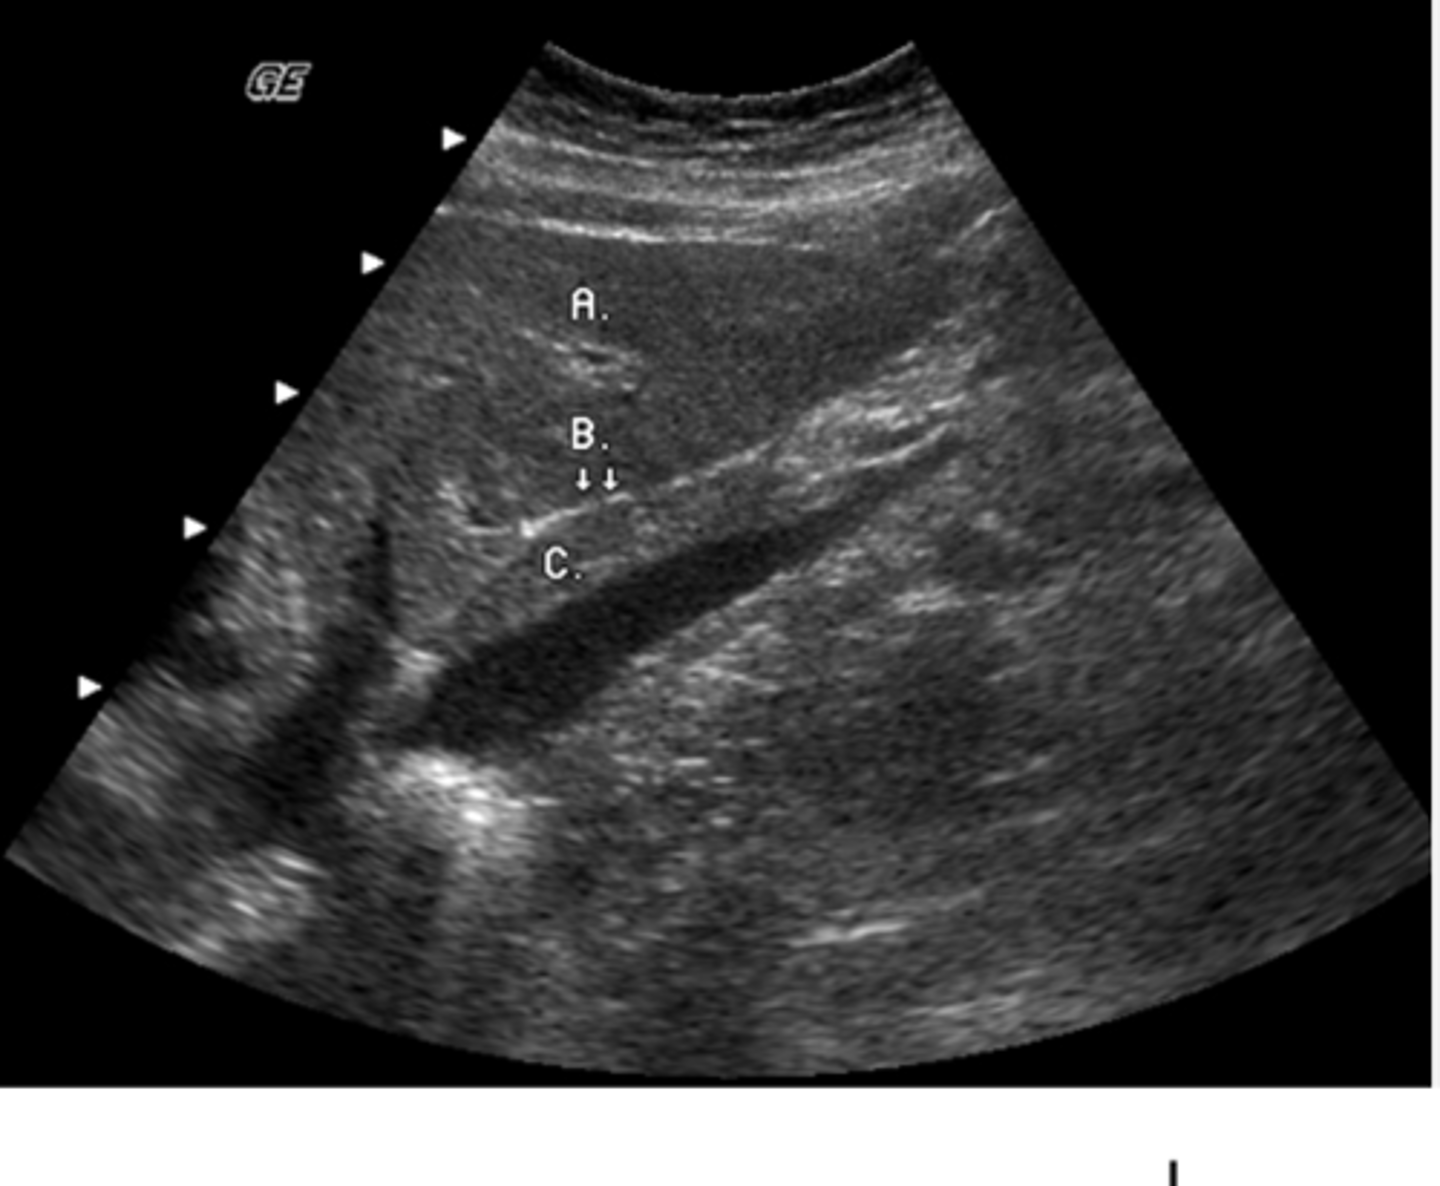

Identify the anatomy labeled "C"

a. aorta

b. portal vein

c. superior mesenteric vein

d. inferior mesenteric vein

e. Inferior vena cava